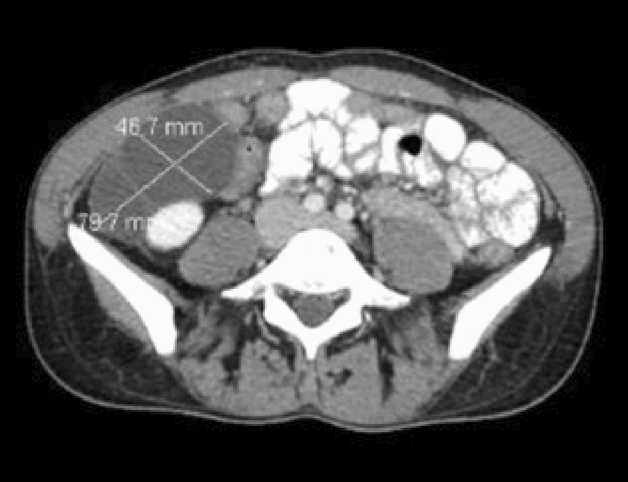

P041